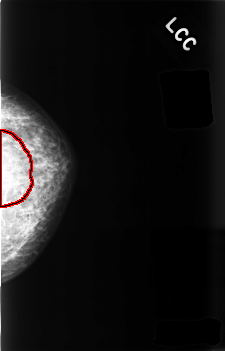

C_0481_1.LEFT_CC

FILE: C_0481_1.LEFT_CC.OVERLAY

TOTAL_ABNORMALITIES 1

ABNORMALITY 1

LESION_TYPE MASS SHAPE ASYMMETRIC_BREAST_TISSUE MARGINS ILL_DEFINED

ASSESSMENT 5

SUBTLETY 2

PATHOLOGY MALIGNANT

TOTAL_OUTLINES 1

BOUNDARY